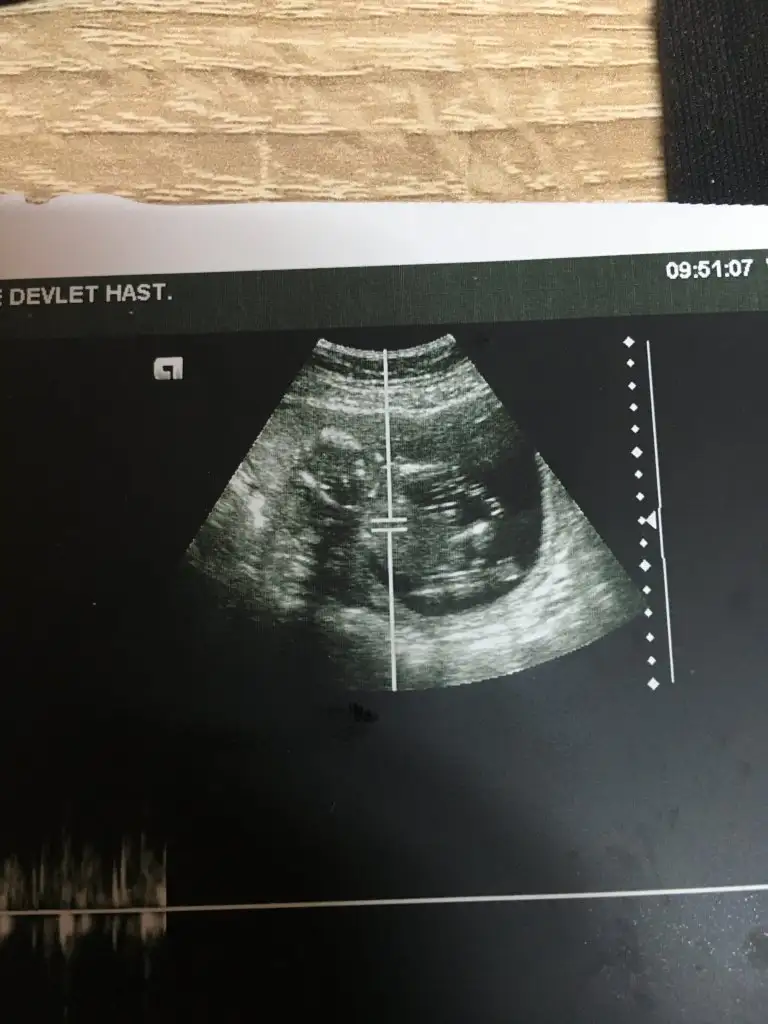

İyi akşamlar benimde 13 haftalık yorumlar mısınız acaba😊

• B5E15C14-1EEF-4073-975F-A94926355663.webp

B5E15C14-1EEF-4073-975F-A94926355663.webp

23 KB · Görüntüleme: 89